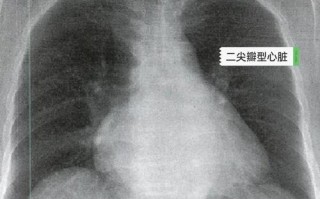

儿童肺动脉段突出究竟是什么原因导致的?

什么是肺动脉段突出?在儿童胸部X光片上,心脏的轮廓通常被描述为一个“靴形”或“斜位”的影子,位于心脏上方、靠近肺门的弧形部分,就是肺动脉段,这个部分是由右心室流出道和肺动脉主干共同构成的,当医生在X光...